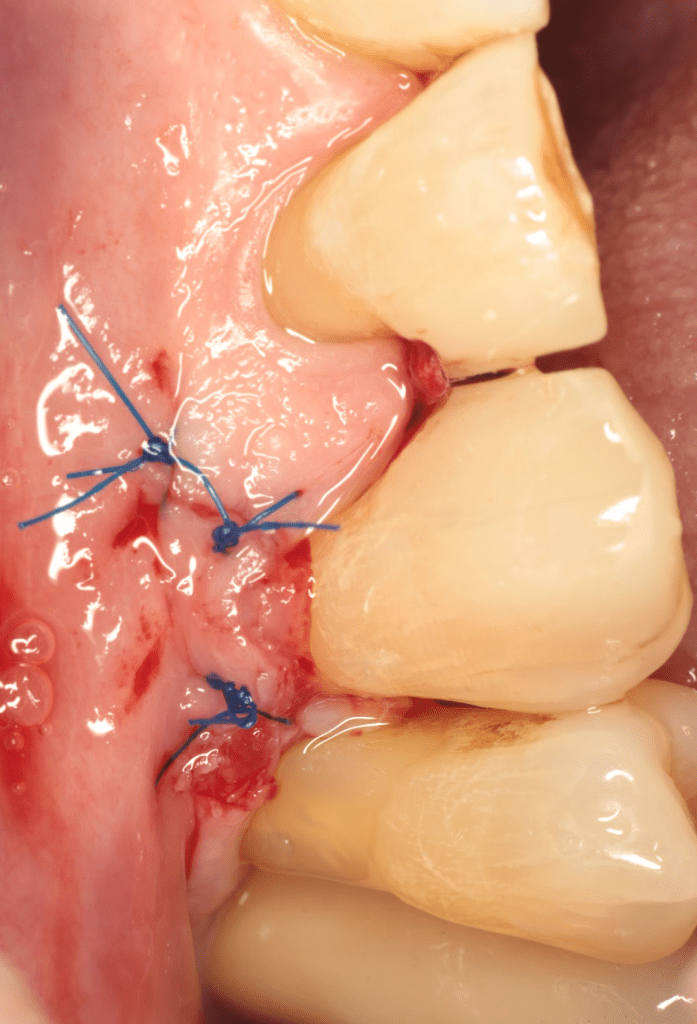

Reconstrucción preendodóntica

Reco pared vesticular

Reco pre-endo gingivectomái, pared yuxtaosea

Reco preendo + gingivectomía